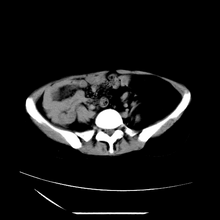

诊断rsl的必备条件是肾窦、肾门的脂肪组织增生和肾实质的萎缩,而且本例因为ivp后扫描不好判断有无肾结石但可能性较小;另外,占位效应显著,脾后缘都受压了,肾门以下肾实质残缺,支持肾脏错构瘤.

左肾周脂肪堆积征【原因?】,双肾逆行造影术后;脾大【原因?】

1、考虑左肾替代性脂肪瘤病,2、双肾积水,3、距脾,4、楼主说的我考虑为感染性病灶。

腹膜后脂肪肉瘤累及左输尿管及左肾窦脂肪沉积,双肾积水,